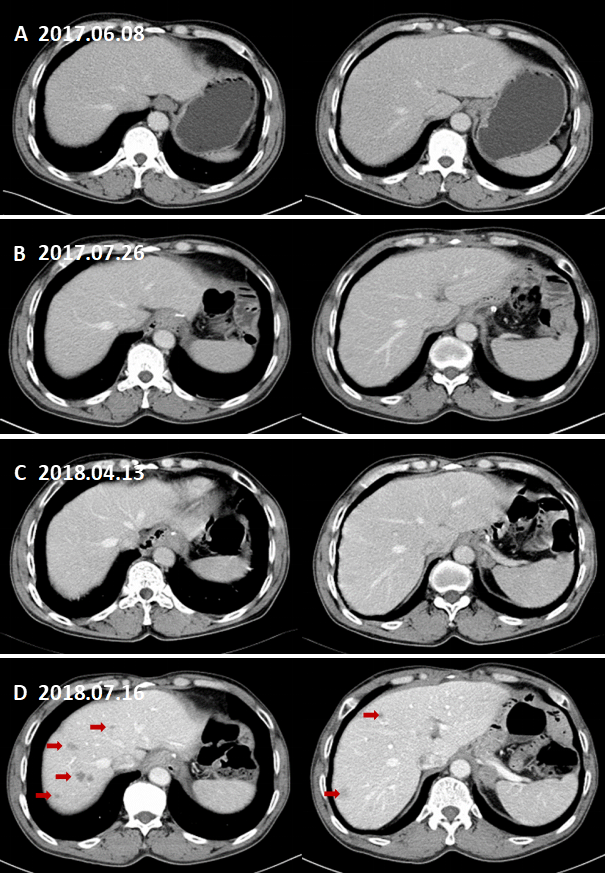

全腹部CT增强扫描(2017.06.08):胃底壁增厚,增强后均匀中度强化,大小范围约20*19mm;伴膈下区一枚肿大淋巴结,大小约10.4*15.4mm。左侧肾上腺增生首先考虑;后腹膜多发小淋巴结。

图1. 代表性术前CT图像。

A:术前CT增强(2017.06.08)示胃底部病灶及膈下淋巴结肿大;B:左侧肾上腺增生首先考虑;后腹膜多发小淋巴结。

(1)全腹部CT增强扫描(2018.04.13):膈下新发淋巴结转移。

图2. 代表性CT图片提示膈下新发淋巴结转移。

A:术前CT增强(2017.06.08)示膈下淋巴结肿大;B:术后CT增强复查(2017.07.26)示膈下未见肿大淋巴结;C、D:术后CT增强复查(2018.04.13)示左侧膈肌后下方2枚新发淋巴结转移。

(2)全腹部CT增强扫描(2018.07.16):膈下淋巴结转移。左侧肾上腺区及腹膜后多发肿大淋巴结,转移考虑,较前片(2018.04.13)增多增大。肝内多发转移瘤。

图3. 膈下淋巴结转移。

A:术前CT增强(2017.06.08)B:术后CT增强复查(2017.07.26)示膈肌脚处未见肿大淋巴结;C:术后CT增强复查(2018.04.13)示左侧膈肌脚处新发肿大淋巴结。D:术后CT增强复查(2018.07.16)示左侧膈肌脚处肿大淋巴结与C相仿。